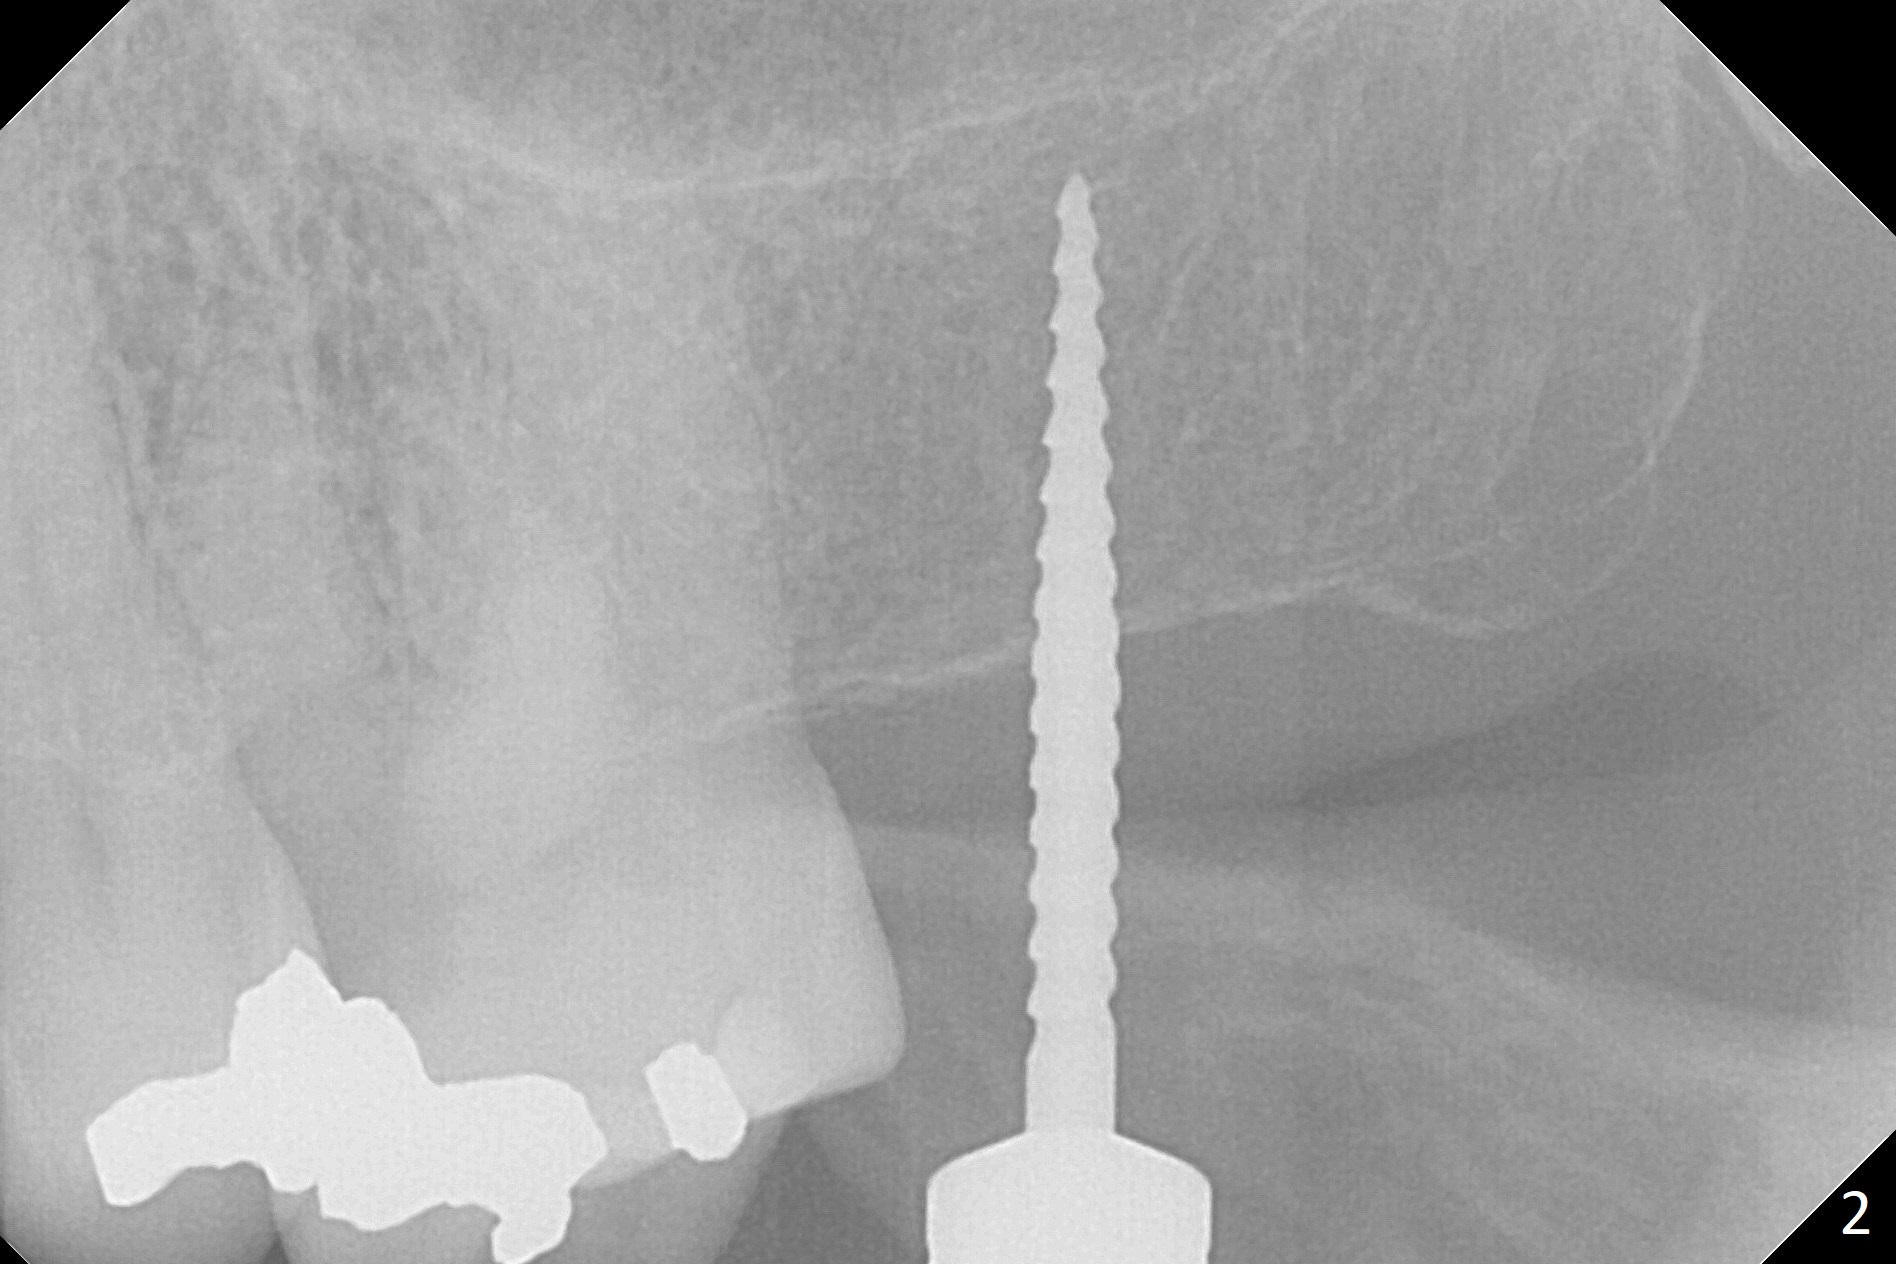

The ridge is pointed at the site of #15 (Fig.1). A 1.2 mm initial drill is used to start osteotomy for 10 mm, followed by an incision over the ridge mesiodistally for ~ 8 mm. After tapping the #15 C blade, the 1st Bone Expander 1.0/1.6 mm) is inserted for ~ 11 mm (Fig.2, 20 Ncm). Bone expansion continues until #4 Expander (2.4/3.7 mm, Fig.3). When 4x11 mm and 4.5x11 mm dummy implants are placed (Fig.4), insertion torque remains 20 Ncm. Following placing allograft with 3-4 amalgam carriers, a 5x11 mm IBS implant is placed with 20 Ncm (Fig.5,6). In fact the implant turns when an abutment is placed. When the implant is re-inserted, torque decreases to 10 Ncm. Instead a healing screw is placed. The low torque value is due to soft bone and failure to underprep. #4 Expander (Fig.3) seems larger than 4.5 mm implant (Fig.4). #3 Expander (1.7/3.1 mm) should have been used prior to definitive implant placement. The implant appears to have osteointegrated 3 months postop (Fig.7); impression is taken. The bone density at the crest increases 1.5 years post cementation (Fig.8 *, as compared to Fig.6), although there is mild bone loss. Implant placement should be deep when bone expansion is carried out. The tooth #14 develops a buccal fistula, corresponding to periapical radiolucency of the mesiobuccal root (Fig.9 white >). The abutment of #15 may be incompletely seated (black <). PA taken when RCT of #14 is finished does not show the incomplete seating of the abutment (Fig.10). Since there appears no history of abutment screw loosening, the abutment is not reseated when #14 is prepared for crown. Recall 3 years 7 months post cementation shows incomplete seating of the abutment (Fig.11 >). After crown proximal reduction (Fig.12 *) and clockwise turn of the crown, the abutment appears to be completely seated. When the case returns from lab, the separate crown and abutment cannot be connected to the fixture because of soft tissue adaptation and change in a month. The abutment is reseated to the fixture analog in the model and the crown is recemented with temp bond (in case of misalignment) while making sure that the crown has the best proximal contact with the neighboring crown. With the abutment and crown in a unit, it is much easier to reseat the abutment with normal proximal contact. The torque is 20 Ncm. The access hole is closed with Cavit.